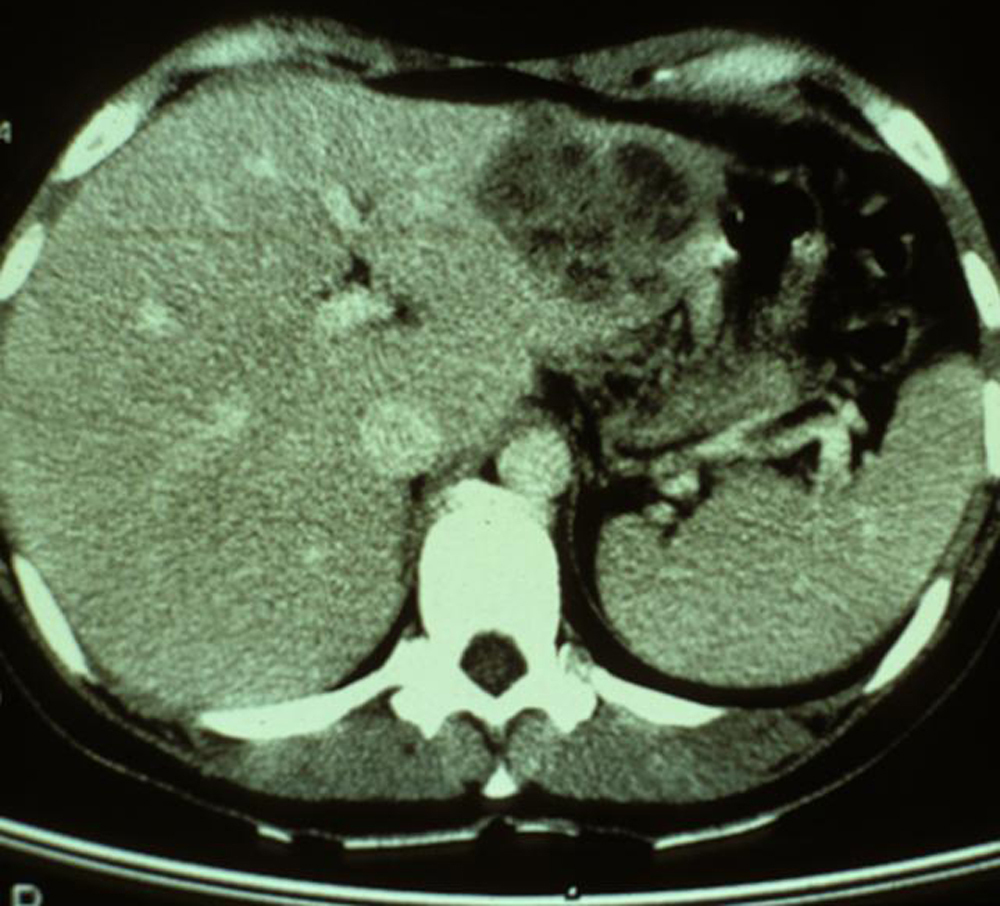

Il s’agit d’une distomatose hépatique ou grande douve du foie due à Fasciola hepatica. Sur cette tomodensitométrie hépatique on observe, outre une hépatomégalie, des images hépatiques hypodenses avec des hématomes sous-capsulaires.